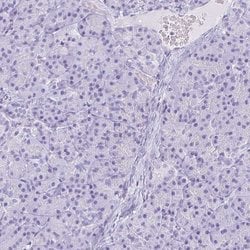

Invitrogen™ NGB Polyclonal Antibody

Brand: Invitrogen™ PA563594

| Immunohistochemistry (Paraffin) | |